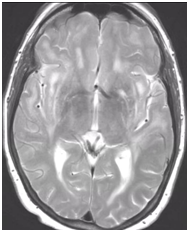

During follow-up in stroke clinic, her imaging was reviewed. MR imaging demonstrated large confluent areas of hyperintense T2 and FLAIR signal abnormality throughout the periventricular and deep white matter with extension into the subcortical white matter (Figure 1) (Figure 2). T1w images demonstrated low signal, corresponding to the T2/FLAIR abnormality on T2w images. This white matter abnormality is known as leukoaraiosis. The hyperintense T2/FLAIR signal abnormality also involved the anterior temporal lobes (Figure 3) (Figure 4) and external capsules (Figure 5) (Figure 6). This feature on MRI is uncharacteristic of other white matter diseases, notably the sporadic subcortical atherosclerotic encephalopathy. In our patient, the corpus callosum was spared. The lacunar infarcts were small vessel infarcts, typically seen in the deep white matter, basal ganglia, thalami, and the pons. On diffusion images, there was a small area of diffusion restriction in the left corona radiata that was consistent with an acute infarct (Figure 7) (Figure 8). Subsequently, there was an area of encephalomalacia on follow-up MRI at the location of the previous acute infarct. This abnormality correlated with the right-sided weakness seen prior to the index patient’s admission.

Figure 2 FLAIR axial image at a higher level demonstrates more conspicuous hyperintense white matter signal abnormality.